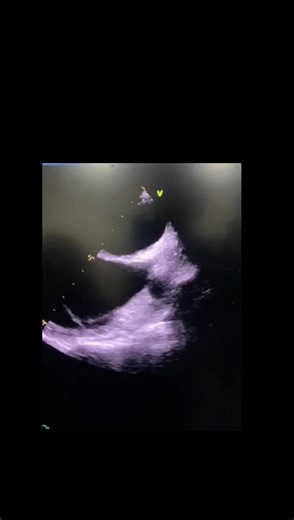

- Bicaval View

Echocardiography - Bicaval View

Bicaval View - Intracardiac

Views - Bicaval View

View - Biatrial vs Bicaval

On Tee - Bicaval